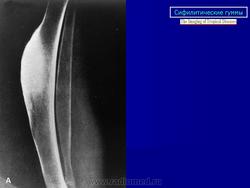

Гуммозный периостит наблюдается в излюбленном месте, в диафизе (чаще большеберцовой кости) - в оссифицированном периосте определяется одна или несколько гумм овальной или округлой формы. На рентгенограммах обычно на уровне диафиза отмечается ограниченное утолщение кости в форме полуверетена за счет утолщения периоста с гладким наружным контуром. Гумма - одна или несколько в виде очага деструкции (размерами не более 1,5-2 см) располагается в самом центральном месте остеофита, непосредственно под надкостницей, с четкими склерозированными контурами.

Диффузный сифилитический остеопериостит при позднем врожденном сифилисе по частоте поражения занимает 1 место. Поражается преимущественно большеберцовая кость. На рентгенограммах утолщенная окостеневшая надкостница сливается с корковым слоем. Во всех слоях кости - массивный склероз, кость на большом протяжении теряет свою структуру. Наружный контур четкий, но может быть несколько волнистым. Среди склероза могут наблюдаться очажки деструкции за счет миллиарных гумм - это сочетание множественного гуммозного и диффузного сифилитического периостита.

При локализации процесса в большеберцовой кости отмечается характерная картина «саблевидной голени» (кость удлинена, утолщена, изгибается кпереди). Редко встречаются «гребневидные» периоститы с наличием поперечных полос, напоминающих зубцы гребня, и «кружевные» периоститы - сочетание слоистого и гребневого периостита, что напоминает кружево. Наружние контуры, как правило, зазубрены.

Раньше работала в больнице, где было отделение по выхаживанию новорожденных. Очень часто встречалась с врожденным сифилисом, которого с каждым годом становится все больше и больше. Основными проявлениями были остеохондрит и сифилитический периостит. Вот несколько снимочков с этой патологией, быть может, кто-то не встречался с ней.